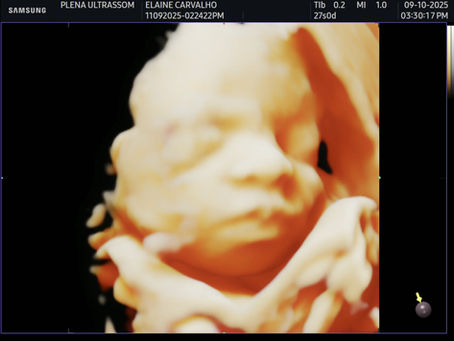

Como obter as melhores fotos de ultrassom 3D?

Se você está grávida, provavelmente já babou pelas fotos sonhadoras de ultrassom 3D. Nos últimos 4 a 5 anos, o ultrassom eletivo se...